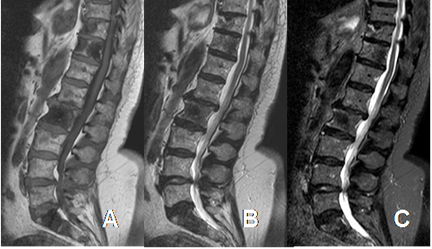

Fig 12. Contraste en RM.

A: RM axial en T1 simple y B: RM axial en T1 con contraste. Enfermedad metastásica pulmonar, con gran masa de tejidos blandos paraespinal y en la parte posterior izquierda del canal, que presenta realce homogéneo del contraste.

Fig 13. Contraste en RM.

A: RM axial en T1 simple y B: RM axial en T1 con contraste. Lesión metastásica que compromete el sacro, con masa de tejidos blandos. Hay realce heterogéneo del contraste, que indica zona de necrosis central. (Flechas).